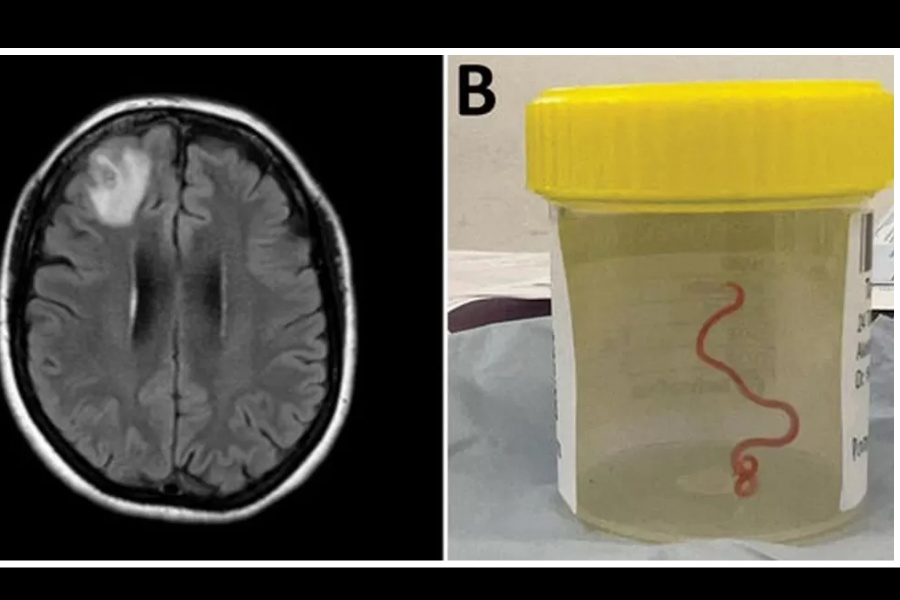

विश्वमै पहिलोपटक भेटियो मानव मस्तिष्कमा जीवित कीरा

जनावरबाट मानिसमा सर्ने रोग र संक्रमणको बढ्दो खतरालाई यस तथ्यले उजागर गरेको अनुसन्धानकर्ताले चेतावनी दिएका छन्।